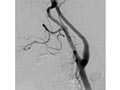

An angiogram of the head and neck is an X-ray test that uses a special dye and imaging (fluoroscopy) to take pictures of the blood flow in the blood vessels of the head and neck . An angiogram of the neck (carotid angiogram) can be used to look at the large arteries in the neck that lead to the brain. An angiogram of the head (cerebral angiogram) can be used to look at the veins or the four arteries (four-vessel study) carrying blood to the brain.

An angiogram can find a bulge in a blood vessel (aneurysm). It can also show narrowing or a blockage in a blood vessel that slows or stops blood flow. An abnormal pattern of blood vessels (arteriovenous [AV] malformation) or abnormal vessels near a tumour can be seen.